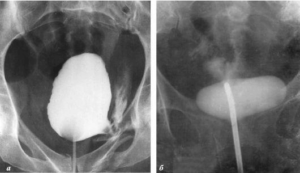

Voglio mostrarvi alcune immagini, in modo che possiate vedere da voi cosa succede al tratto urogenitale e agli altri organi di un uomo che non fa sesso.

Ecco come appare l’infiammazione prostata causata dal ristagno di spermatozoi (quando i testicoli non vengono svuotati). L’infiammazione persistente porta dapprima all’adenoma prostatico, e successivamente al tumore alla prostata (in base alle statistiche, il 38% degli uomini muore per questo motivo). In mancanza di sesso, questo succede sempre ed è per questo che l’adenoma prostatico viene chiamato “la malattia degli anziani”.